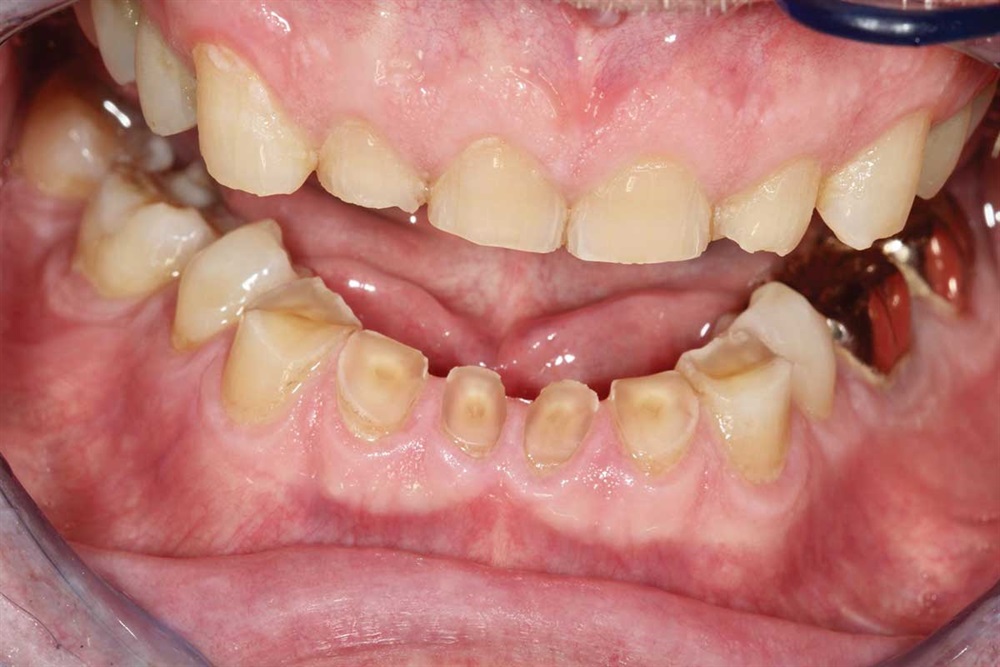

Fig. 1: June 2018. Where did all the tooth structure go? Grinding in protrusion? There is serious wear and tear. This 63-year-old gentleman has been wearing out his teeth, especially in the past 10 years.

Show Your Work

Fig. 3: Lower incisors. The patient’s dentists in Ontario wanted to do ortho for 18–24 months and then restorative crowns with many elective root canals, to the tune of a nice luxury car.